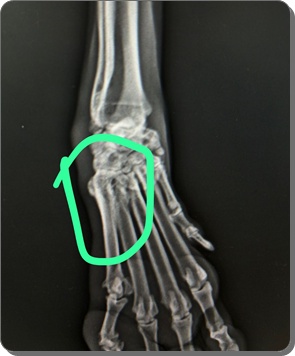

In der Röntgenuntersuchung der Gliedmaßen wurden Veränderungen festgestellt,

die auf eine beginnende Osteoporose hinweisen, sodass die Knochenstruktur

als nicht gesund bewertet wird und eine erhöhte Fragilität

(leichteres Brechen) anzunehmen ist.